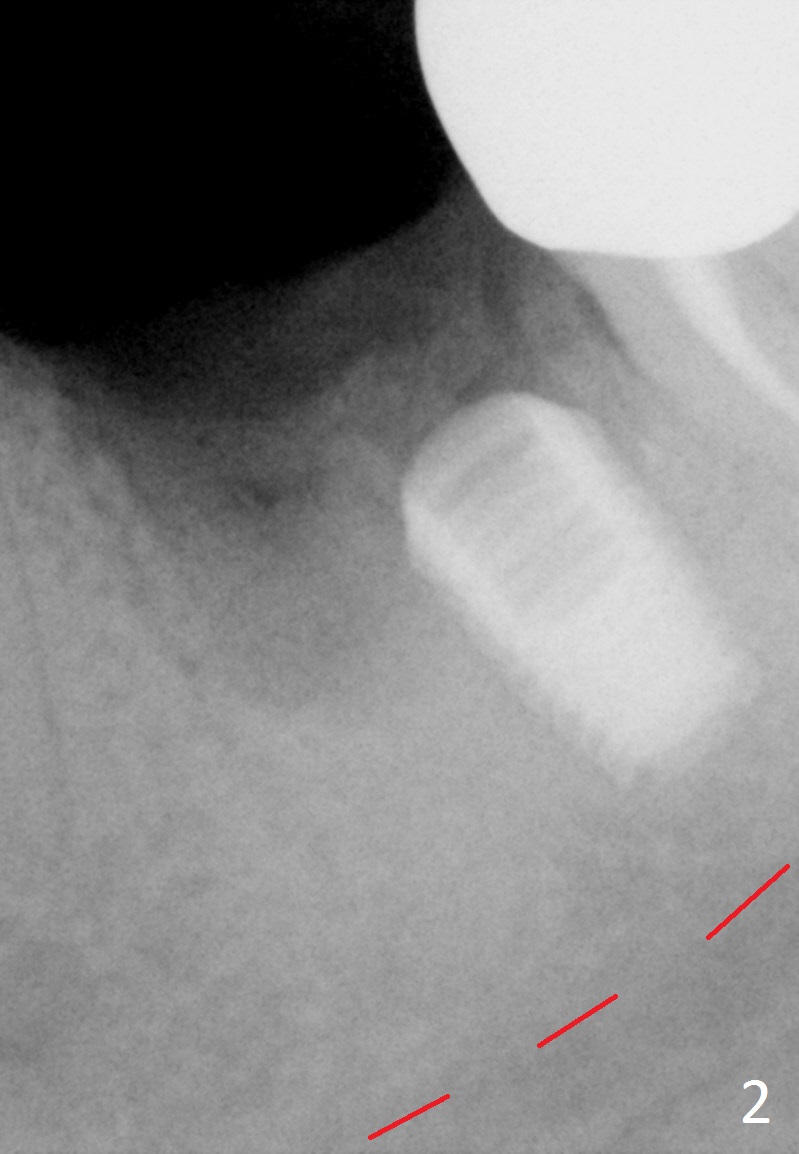

A 42-year-old woman presented to clinic 11 years ago with history of extraction of the tooth #19 two months earlier (Fig.1).  Two months later, a 5x8 mm Bicon implant was placed (Fig.2).  Integrated Abutment Crown was delivered 2 years later (Fig.3) with persistent radiolucency in the mesial socket.  The tooth #18 was extracted with socket preservation 7 years ago.  Recently she returned with chief complaint of chewing pain in the lower left for a while.  The buccal gingiva of #19 is erythematous, edematous and tender (Fig.4).  There are healing abutment at #29 and implant crown at #30.